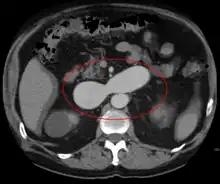

AVMs are diagnosed primarily by the following imaging methods:[12]

- Computerized tomography (CT) scan is a noninvasive X-ray to view the anatomical structures within the brain to detect blood in or around the brain. A newer technology called CT angiography involves the injection of contrast into the blood stream to view the arteries of the brain. This type of test provides the best pictures of blood vessels through angiography and soft tissues through CT.

- Magnetic resonance imaging (MRI) scan is a noninvasive test, which uses a magnetic field and radio-frequency waves to give a detailed view of the soft tissues of the brain.

- Magnetic resonance angiography (MRA) – scans created using magnetic resonance imaging to specifically image the blood vessels and structures of the brain. A magnetic resonance angiogram can be an invasive procedure, involving the introduction of contrast dyes (e.g., gadolinium MR contrast agents) into the vasculature (circulatory system) of a patient using a catheter inserted into an artery and passed through the blood vessels to the brain. Once the catheter is in place, the contrast dye is injected into the bloodstream and the MR images are taken. Additionally or alternatively, flow-dependent or other contrast-free magnetic resonance imaging techniques can be used to determine the location and other properties of the vasculature.